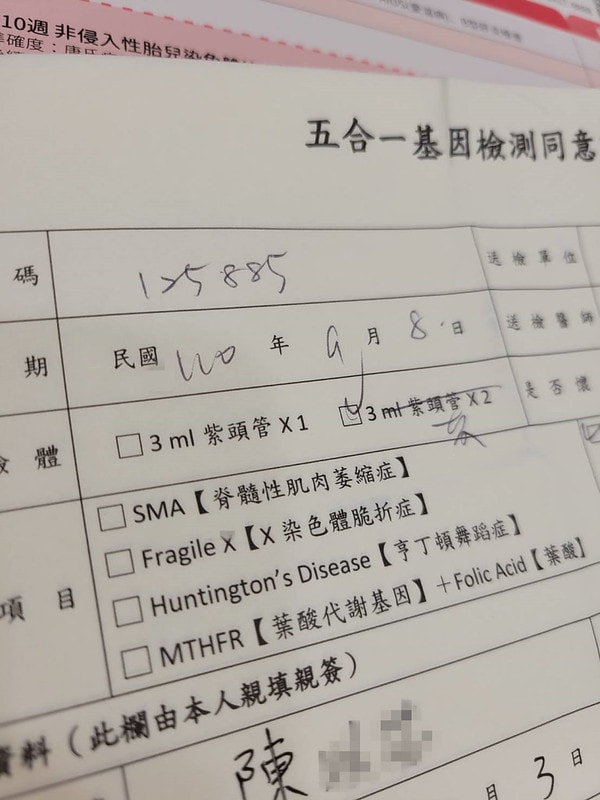

然後就是要填一堆表格

五合一基因檢測只有第一次懷孕要做

脊髓性肌肉萎縮症

X染色體脆折症

亨丁頓舞蹈症

葉酸代謝基因跟葉酸

之後如果要生二胎或是三胎就不用了

費用大概是5500左右

這部分的檢查

我後來是都沒有問題

葉酸也算偏高